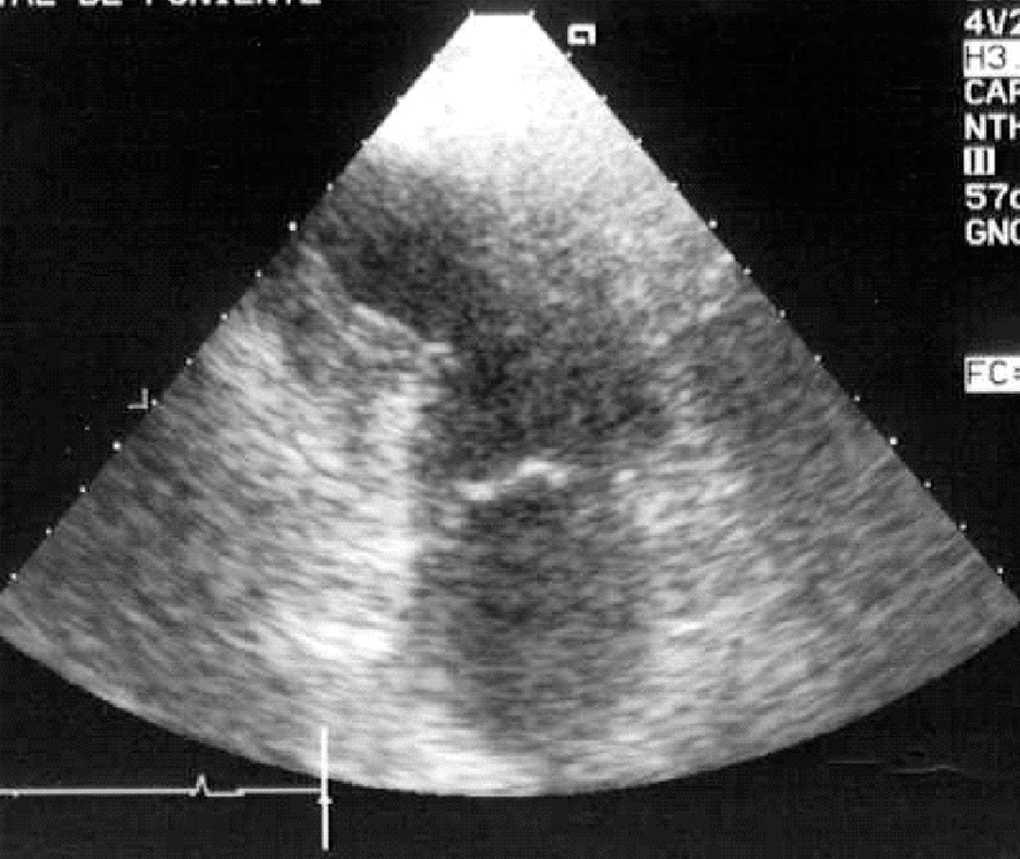

Aparte de la heterogeneidad de las distintas descripciones, de todos los estudios publicados se desprende que en presencia de patología neurológica grave se puede producir una disfunción miocárdica con una incidencia desconocida, pero que podría estar en torno al 9%, que mejora habitualmente en la primera semana, y es reversible en la mayoría de los supervivientes entre el primer y el sexto mes. Aunque la causa del fallecimiento es dependiente de la propia patología cerebral, dicha disfunción miocárdica reversible puede contribuir a la mortalidad, o al menos incrementar la morbilidad al poder cursar con complicaciones tales como arritmias potencialmente letales15,29, hipotensión arterial, edema pulmonar15,29, hipoxemia13-21, que podrían potenciar las lesiones cerebrales secundarias, así como formación de trombos intracavitarios en el ventrículo izquierdo12,14,15,18 que podrían provocar embolias15 (fig. 2). Por otra parte, esta disfunción miocárdica puede ser una causa directa del edema neurogénico o al menos contribuir a su desarrollo, ya sea por la propia disfunción ventricular sistólica o por otras complicaciones asociadas, tales como una insuficiencia mitral grave (figs. 3 y 4).

Figura 2. Ecocardiografía transtorácica, plano apical 4 cámaras, donde puede observarse una imagen de trombo y ecocontraste espontáneo en el ventrículo izquierdo de un paciente de 21 años con hemorragia subaracnoidea e hipoquinesia ventricular izquierda global grave.